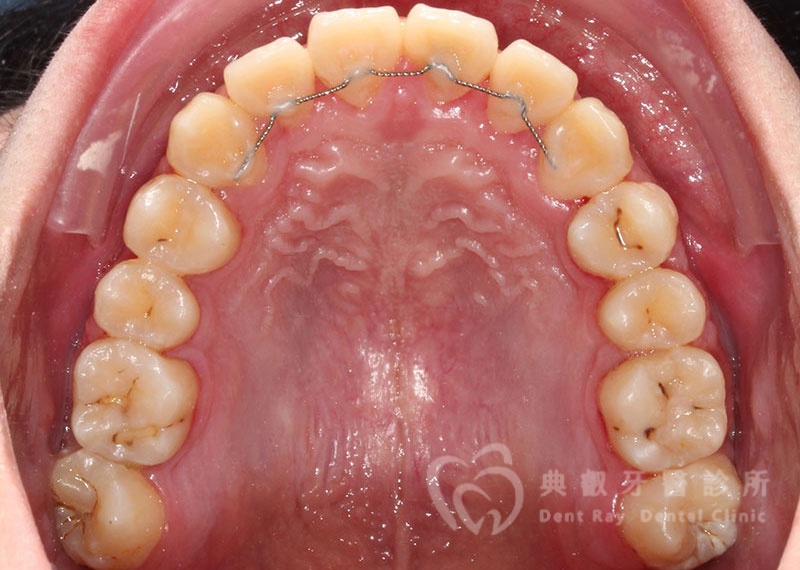

Before

After